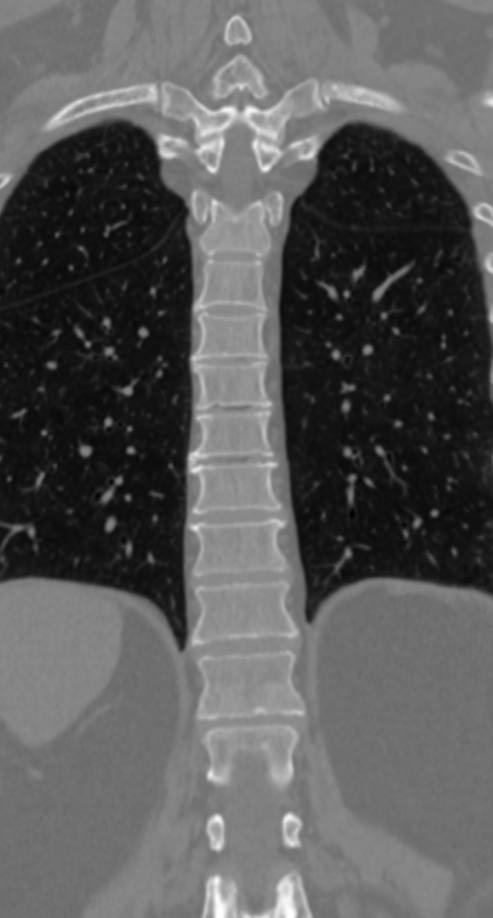

Мультиспиральная компьютерная томография является одним из наиболее информативных методов диагностики дегенеративно-дистрофических заболеваний, травматических, воспалительных изменений, а также опухолевых процессов позвоночника. Методика предусматривает использование рентгеновского излучения для получения детализированных снимков костных структур позвоночника, межпозвонковых суставов и межпозвоночных дисков.

При подозрении на распространенный процесс с поражением различных уровней позвоночного столба показано проведение мультиспиральной КТ трех отделов позвоночника.

В клинике «Доступная медицина» установлены современные мультиспиральные компьютерные томографы экспертного класса TOSHIBA AQUILION в различных модификациях (64-срезовый и 128-срезовый), на которых выполняются комплексные обследования позвоночника, включая одномоментное исследование несколько отделов. Аппараты производят сканирование с помощью рентгеновских лучей, делая тончайшие срезы с шагом от 0,5 мм, затем с помощью компьютерных программ полученные данные преобразуются в изображения трехмерного формата, что обеспечивает точность и достоверность диагностики.

Что покажет КТ трех отделов позвоночника

С помощью мультиспиральной КТ можно диагностировать:

- патологические изгибы позвоночника, сколиоз, усиленный или выпрямленный лордоз как нарушение статической функции позвоночника;